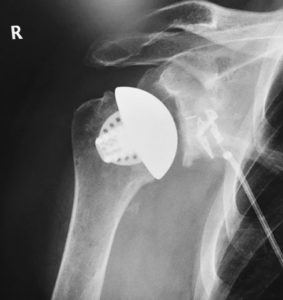

Equinoxe Stemless (sin vástago) es una prótesis conservadora de hueso diseñada para la artroplastia anatómica total del hombro. La estructura porosa impresa en 3D facilita la fijación biológica y la jaula ósea promueve el crecimiento óseo.